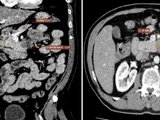

Theo TS.BS Đỗ Anh Tú, Phó Giám đốc Bệnh viện K, xa trị có khả năng tiêu diệt tế bào ung thư, ngăn ngừa sự phát triển của chúng, và thậm chí có thể điều trị giảm nhẹ các triệu chứng khi ung thư ở giai đoạn cuối. Xạ trị có thể được sử dụng để điều trị nhiều loại ung thư ở hầu hết các bộ phận trên cơ thể.

Xạ trị ung thư ngày nay không chỉ là phương pháp điều trị hỗ trợ, mà còn giữ vai trò then chốt trong toàn bộ quá trình điều trị ung thư. Nhờ sự phát triển của công nghệ xạ trị hiện đại, việc điều trị ngày càng chính xác, ít tác dụng phụ và phù hợp với từng người bệnh hơn bao giờ hết.